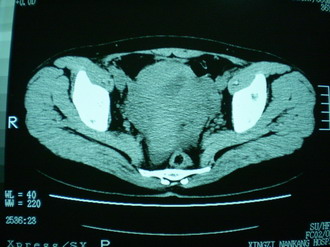

子宫明显前倾,增大,宫颈增大呈分叶状。子宫直肠窝见不规则形水样低密度。(膀胱胀尿不理想)

考虑:1、宫颈部占位;

2、子宫直肠窝少量积液(盆腔炎所致)。

宫颈部肌瘤宫腔内积血,

考虑肌瘤堵塞子宫颈管导致宫腔积液。

考虑:1、宫颈部占位(宫颈癌?);

2、子宫直肠窝少量积液。